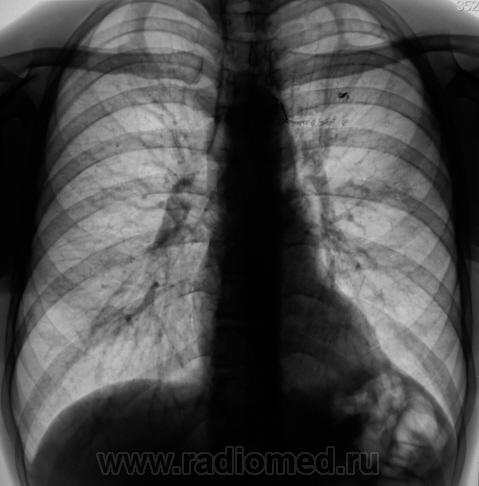

Пациент прооперирован - лобъектомия.

После операции.